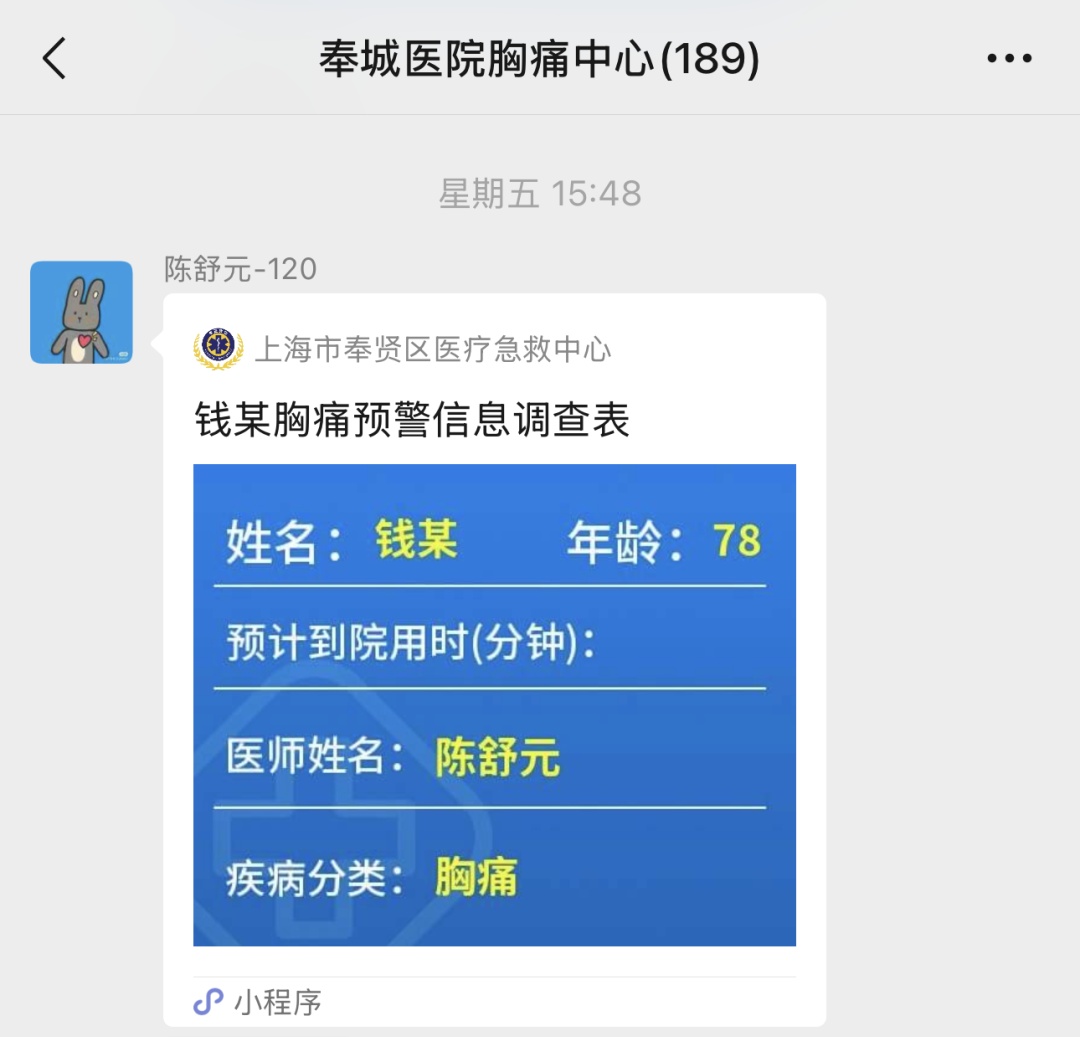

“胸部突然持续性剧烈疼痛,胸口还闷得像压了块石头……” 日前,奉贤四团镇平安渔洋村的78岁钱老伯,在家里突然一阵胸骨后剧痛袭来。此刻他还不知道,一场与死神的赛跑,已在奉城医联体的紧密协作中骤然启动。 社区卫生服务中心里的 “生命侦察兵” “大爷,您这症状不对劲!” 四团镇社区卫生服务中心接诊的卫萍医生触摸到钱老伯冰凉的汗手,立刻警觉起来。心电图机飞速运转,屏幕上清晰显示“急性下壁ST段抬高型心肌梗塞死”,急性心肌梗死死亡风险很高,最佳的治疗措施就是再灌注治疗,在最短的时间内恢复心肌血液供应。可以大幅度降低死亡风险。 “快!启动医联体绿色通道!” 卫医生迅速实施抗血小板负荷治疗,同时拨打120,将心电图通过医联体信息平台实时传输至奉城医院。短短3分钟内,患者姓名、年龄、病史、心电图数据已全部呈现在奉城医院—四团镇社区卫生服务中心沟通群里。 “就像给心脏装‘预警雷达’,基层医生就是发现险情的第一道岗哨。” 奉城医院胸痛中心董照辉主任事后回忆,正是这条 “带图预警” 的信息,让医院提前15分钟启动抢救预案。 从社区到医院 创62分钟奇迹 120救护车呼啸穿行在川南奉公路时,奉城医院急诊室门口已有护士准备接诊,导管室护士紧急术前准备,心内科董照辉主任提前赶到急诊科等待患者到来,迅速查看病人评估病情,就连电梯都被临时调度为“急救专用”,将患者送到导管室。 手术台上,医疗团队默契配合。冠状动脉造影显示:右冠状动脉远段完全闭塞。 董照辉主任快速送入导引导管,PTCA导丝穿过闭塞血管送到远端,球囊扩张后患者血压突然下降,监护仪警报骤响:“血压85/50mmHg!”。 面对这一紧急状况,手术团队临危不乱,立即给予多巴胺升压治疗,并快速补液。血压很快恢复正常,造影右冠远段残余狭窄较重,植入药物支架后,血流恢复正常,缺血缺氧的心肌细胞得到了灌注。 冠状动脉造影示:右冠状动脉远段闭塞 植入药物支架,高压球囊高压后扩张后的,血流恢复,支架贴壁良好 从入院到血管再通,仅用62分钟,比国际标准的90分钟整整快了28分钟!当显示屏上呈现出血流顺畅的图像时,医护人员的手术衣早已被汗水浸透。术后,在医护团队的精心治疗与护理下,钱老伯恢复顺利,10天后康复出院。 让急救链条“咬合”更紧 这场抢救的关键,在于奉城医院医联体构建的“三级急救网络”: 社区筛查层:四团镇社区卫生服务中心等基层机构配备心电图机和医联体传输系统,实现“发病即预警”。 转运衔接层:120救护车医务人员与医院实时沟通共享生命体征数据,途中完成“预入院”登记。 中心救治层:急诊迅速评估病情,检查心电图等,快速转导管室急诊冠状动脉造影。 数据显示,奉城医院胸痛中心运行以来,急性心梗患者平均 Door-to-Balloon时间(入院到血管开通)从110分钟缩短至72分钟,抢救成功率提升18%。 在奉城医院医联体的各个角落,无数医护人员仍在重复着这样的生命接力——他们用脚步丈量急救半径,用数据缩短抢救时间,让“黄金120分钟”里的每一秒,都成为守护生命的勋章。 上海市奉贤区奉城医院 心内科 Cardiology 多年来奉城医院心内科不断提高医疗服务质量,不断开展新技术新项目,让地区居民在奉城就能享受到上海三级医院的心脏介入诊疗项目,为患者的心脏健康保驾护航! 开展心内科常见病及多发病诊疗: 如冠心病、高血压、心力衰竭、心律失常等,接诊疑难急危重症的救治。 开展冠心病介入诊疗手术: 冠状动脉造影术(CAG)、经皮冠状动脉内球囊扩张成形术(PTCA)、经皮冠状动脉内药物洗脱球囊扩张成形术(DCB)、冠状动脉内支架术(STENTS)、主动脉内球囊反搏术(IABP)、血管内超声术(IVUS)、冠状动脉血流储备分数测量术(FFR)等,精准诊断冠心病,规范选择药物球囊或支架术治疗,合理规范药物治疗。开展心律失常介入诊疗手术:腔内电生理检查、阵发性室上性心动过速射频消融术、房颤射频消融术、永久性心脏起搏器安置术等。